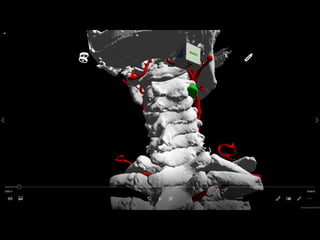

Solution: customized VR App for each

patients

Segmentation

Marching Cube

Polygon

Deep Learning 放射線技師